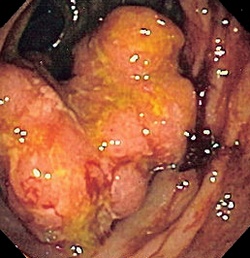

C21 Злокачественное новообразование заднего прохода [ануса] и анального канала